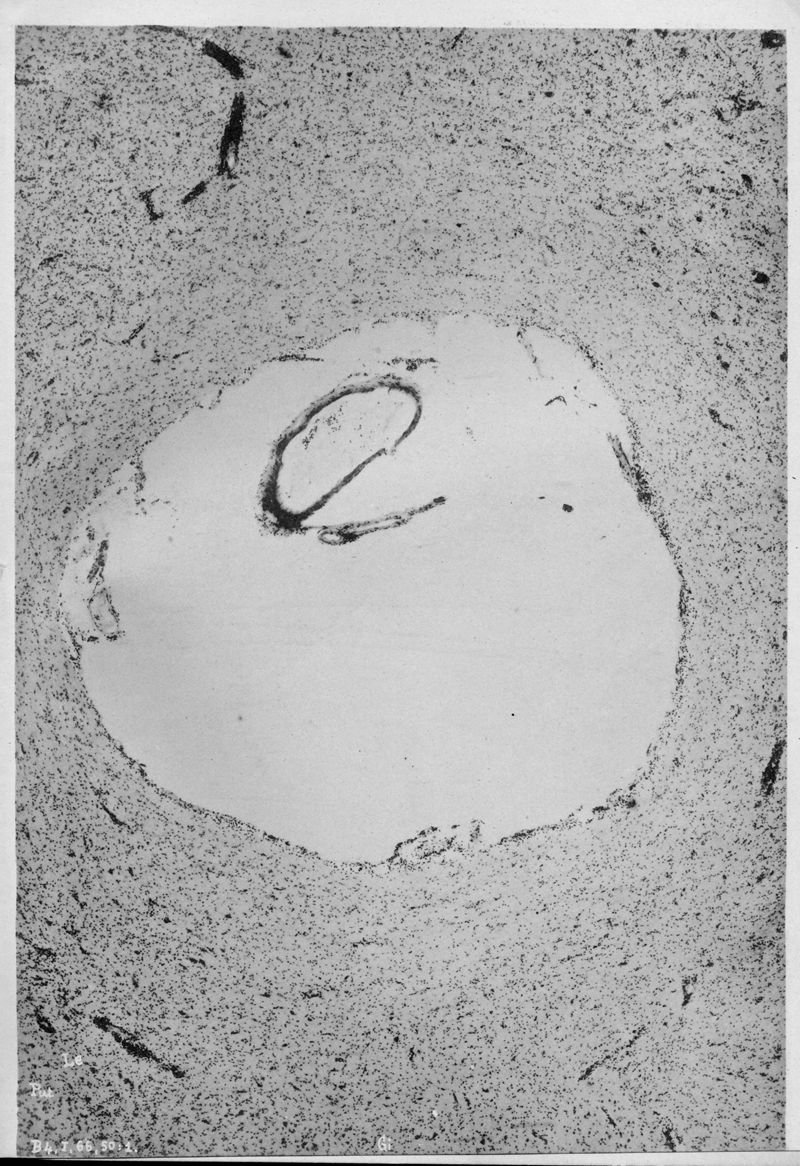

VOGT, Cécile / VOGT, O.

In : Journal für Psychologie und Neurologie,

1920, Vol. 25, pp. 627-846